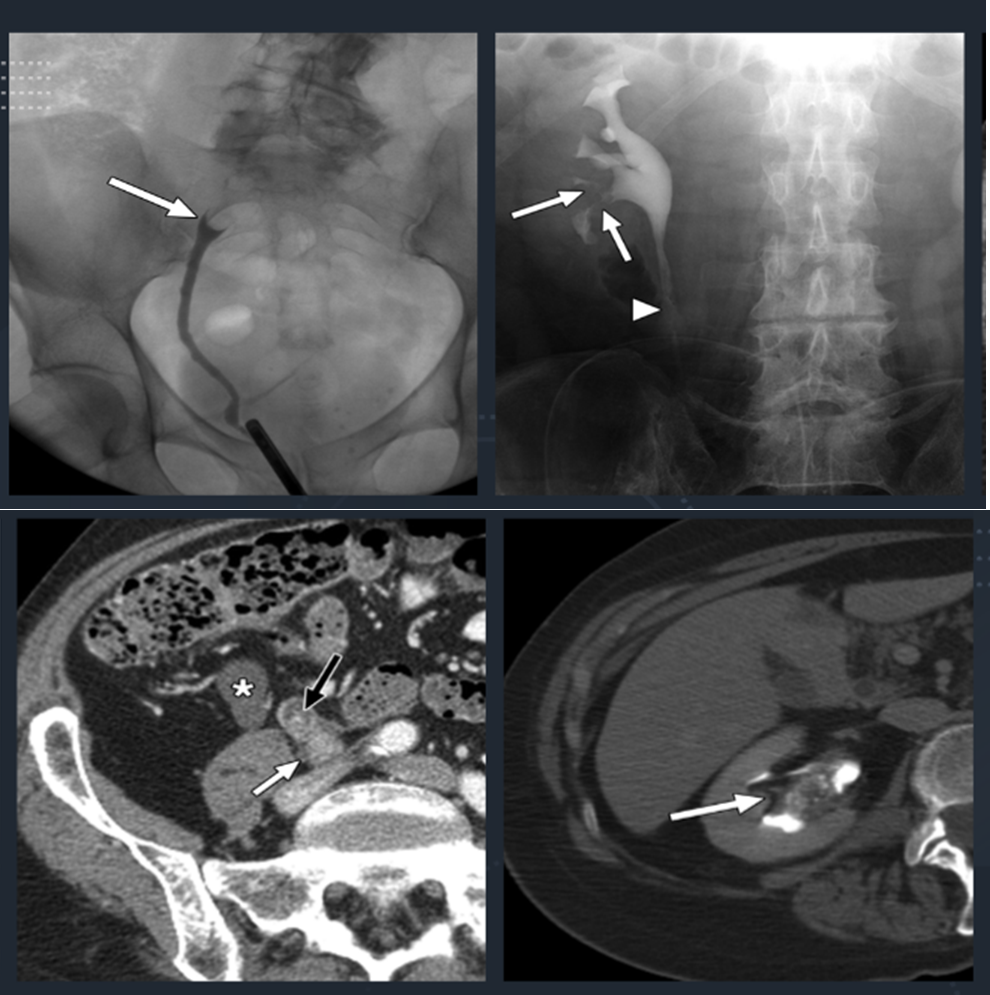

Figure 5: Radiograph and CT depiction of 'filling defects' corresponding to contrast delineating the passable lumen of the urinary tract. Source: https://ajronline.org/doi/full/10.2214/ajr.09.2577

- CT and MRI Urography: Urography lets clinicians visualize the course of contrast along the urinary tract, and may be applied to x-ray, magnetic resonance imaging (MRI), and computed tomography (CT). Intravenous (IV) contrast agents take time to enter and opacify the upper tract lumen, which is why this is called ‘delayed phase’. The use of CT urography is preferred because it has been shown to be the most reliable (Figure 5) (EAU Guideline, Section 5.7 – Strong Recommendation).43 MRI urography is useful when CT is contraindicated (EAU Guideline, Section 5.7 – Weak Recommendation). It is also important to note that other conditions, such as fibroepithelial polyps, inverted papilloma, and fibromas, can also cause upper tract masses and associated tissue-attenuation filling defects.

- Retrograde Pyelogram: In cases where ureteroscopy is unsafe or not possible, selective upper tract washing or barbotage for cytology is recommended, followed by pyeloureterography when high-quality imaging is difficult (Conditional Recommendation; Evidence Level: Grade C; AUA Guideline Statement 5).

Diagnostic Objective: To delineate the upper urinary tract including presence of stricture or other intrinsic causes of ureteral obstruction.